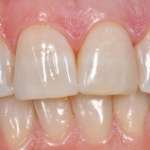

Il recupero estetico-funzionale del settore anteriore con tecniche minimamente invasive

L’obiettivo fondamentale di una riabilitazione estetica sugli elementi anteriori è realizzare denti con proporzioni intrinseche piacevoli, nel rispetto di una corretta integrazione biologica e funzionale, in armonia con i tessuti gengivali.